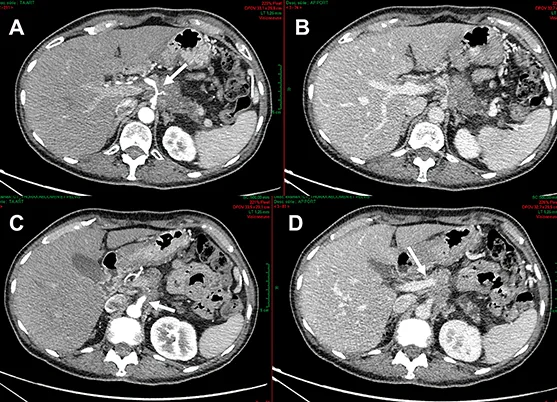

Figure 5 : AP borderline avant et après 6 cycles de chimiothérapie par mFOLFIRINOX. Réponse RECIST, avec persistance des contacts vasculaires

Les données de la littérature concernant l’efficacité du scanner pour déterminer les possibilités de résection chirurgicale après traitement néoadjuvant sont à peu près toutes concordantes (48-50). Autant le scanner est précis en termes de prédiction de la résécabilité R0 avant chirurgie (efficacité de prédiction supérieure à 80 %) autant il est peu spécifique après traitement d’induction (efficacité de prédiction < 60 %). Dans l’étude de Cassinoto et al. il était mentionné une surestimation de la taille avec une variabilité de 10 mm après traitement d’induction et 12 des 31 patients évalué avec risque de résection R1 sur les données scanographiques étaient finalement R0 après traitement d’induction (48). Ainsi il était conclu que seule l’exploration chirurgicale permettait de conclure sur le statut de résection. Le bilan de réévaluation morphologique doit donc s’intéresser à la taille tumorale mais aussi et surtout à l’interface entre la tumeur et les vaisseaux en évaluant la longueur de l’interface tumorale, le degré d’atteinte circonférentielle et les contours vasculaires avec ou sans déformation (51).